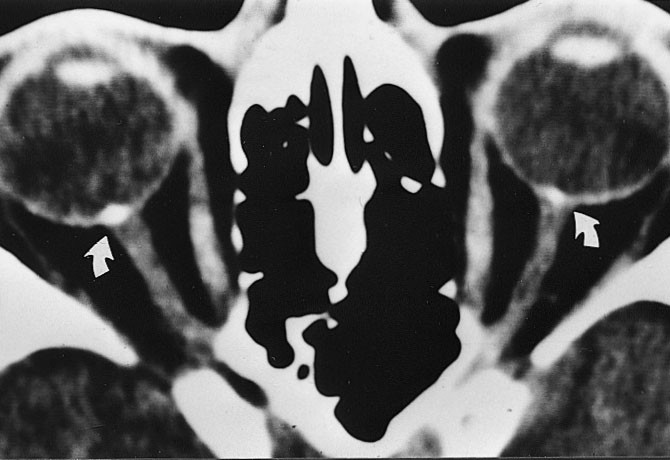

CT med koronalt og aksialt snitt er å foretrekke ved endokrin oftalmopati. Et karakteristisk CT-funn er en relativt symmetrisk forstørrelse, først og fremst av nedre og mediale rette øyemuskler. I 90 % av tilfellene kan det avdekkes patologiske forhold bilateralt, til tross for ensidige symptomer. Aksiale og koronale plan viser godt fordelingen og graden av muskelforstørrelse og forholdet til synsnerven ved orbital apex (8). Det er en relativ sparing av muskelsenen, mens det er særlig fortykket midtre og bakre del ved muskelbunten som er typisk og muliggjør differensiering fra myositt. Endokrin oftalmopati forekommer i 2 – 7 % av tilfellene av Graves sykdom, i aktiv fase med inflammasjon og lymfocyttinfiltrasjon i retrobulbært orbitalt vev, i utbrenningsfasen med fibroser. Et fokalt lavattenuerende område innenfor muskelbunten er et annet CT-funn som tyder på endokrin oftalmopati. Tidlig i forløpet finnes lymfocytisk infiltrasjon og fokal mukopolysakkaridavleiring, mens fettinfiltrasjon forekommer i den senere fasen. Andre hyppige funn ved Graves sykdom er ekspansjon av det orbitale fett, som presser orbitalseptum fremover og dermed strekker synsnerven.

Ved MR-undersøkelse med STIR-frekvens (fettsuppresjon) kan man grunnet økt vanninnhold påvise høysignalområder i aktiv fase i fortykkede muskler (fig 7 a, b). MR kan gi opplysning om muskelkontraktilitet ved repetisjon over flere minutter. Dette kan hjelpe til å oppdage subklinisk sykdom og demonstrerer det naturlige forløpet av sykdommen. Strabismeoperasjon bør utsettes til det ikke påvises noen aktivitet i sykdommen i en eller flere muskler, og botulinumtoksininjeksjon bør unngås hvis muskelen er klart fibrotisk og rigid. Immunsuppressiv behandling bør bare gis ved aktiv sykdom, når inflammasjon er påvist ved STIR-teknikk (9).